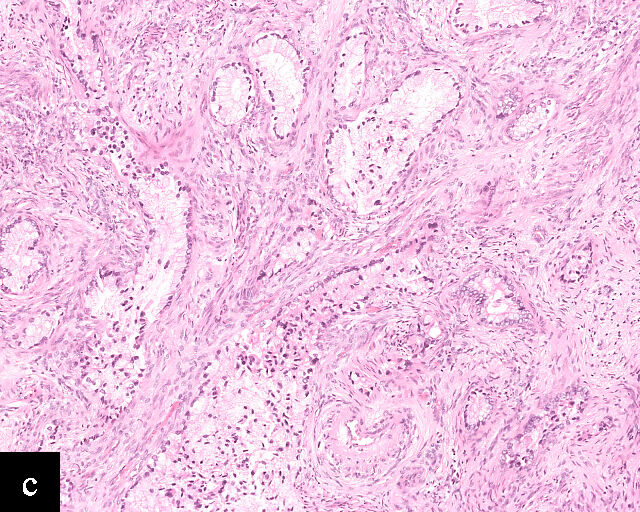

1

Histological sections of HPV-associated carcinoma of the cervix. Squamous cell carcinoma (magnification ×40; a,b) and adenocarcinoma (magnification ×20; c,d), shown with H&E stain (a,c) and p16 immunohistochemistry (b,d).